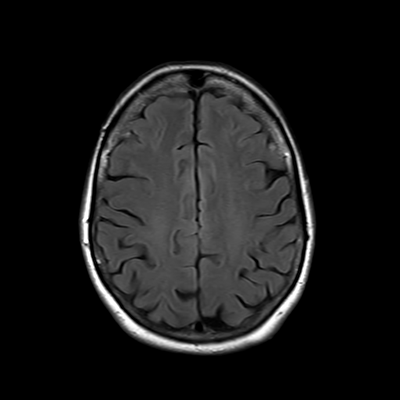

You also obtain an MRI of his brain once it's clinically safe to do so.

MRI brain (FLAIR)

You are now very concerned that he truly has an infectious meningoencephalitis.